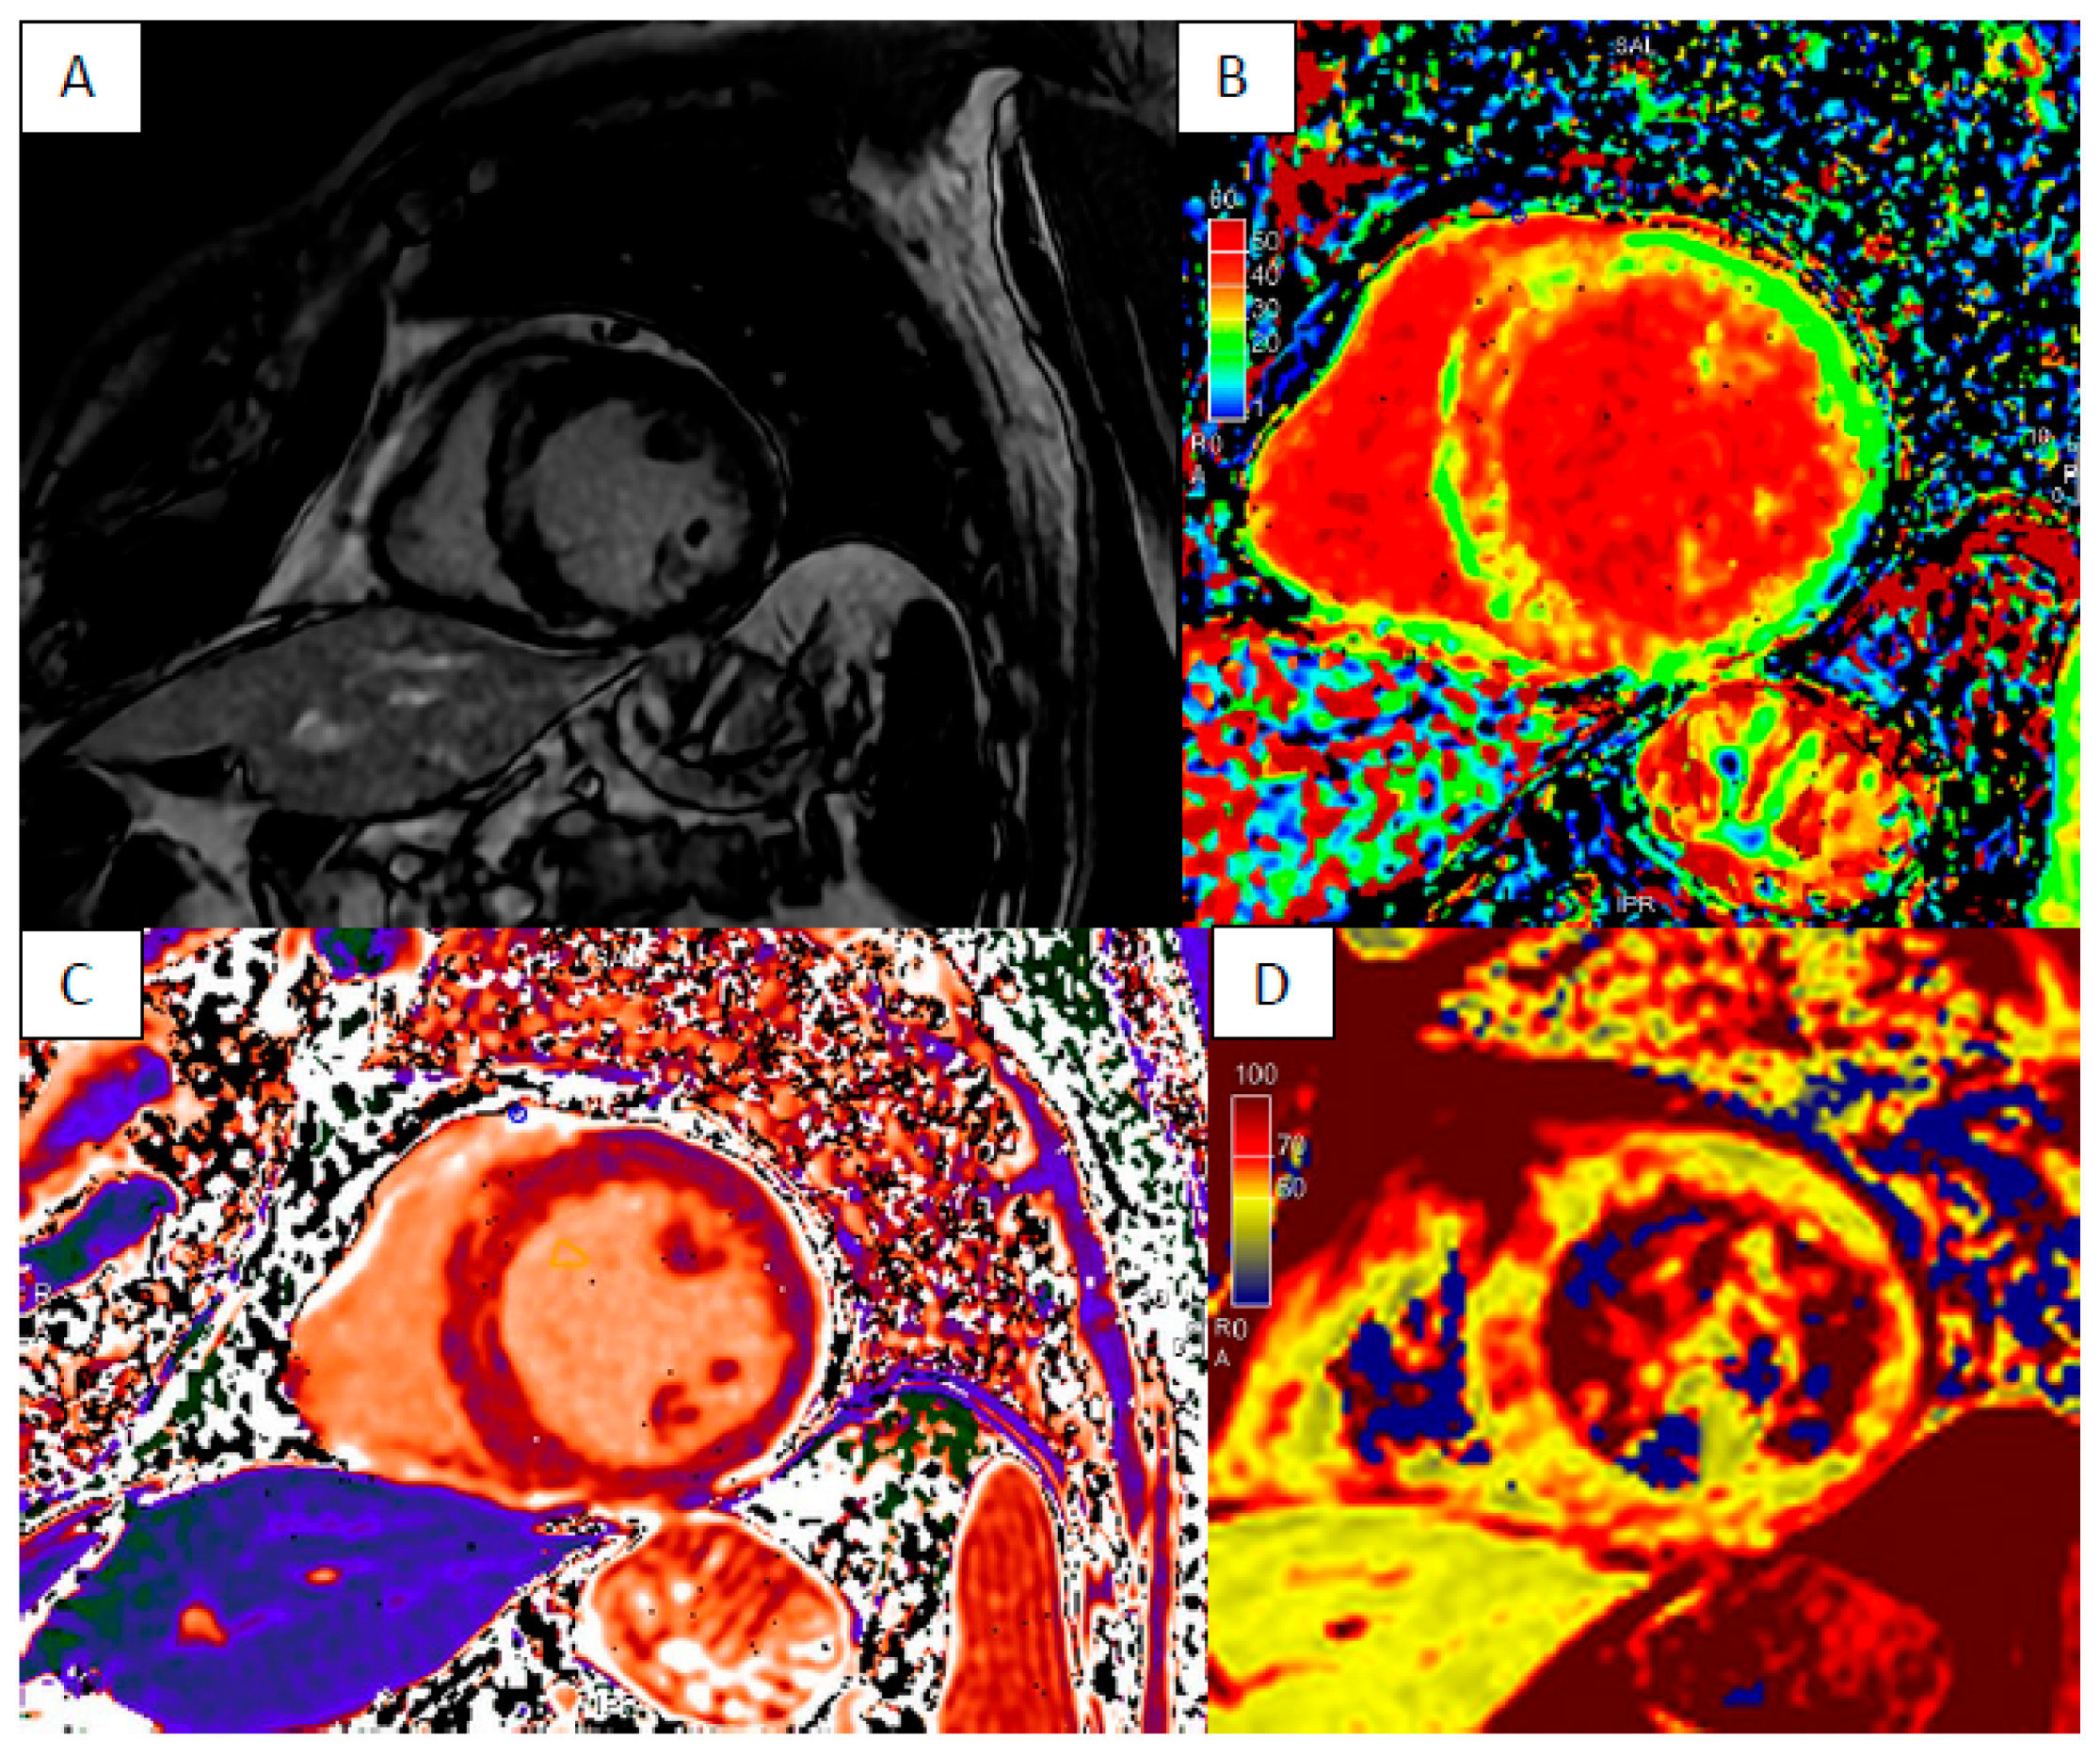

3. Cardiac Sarcoidosis